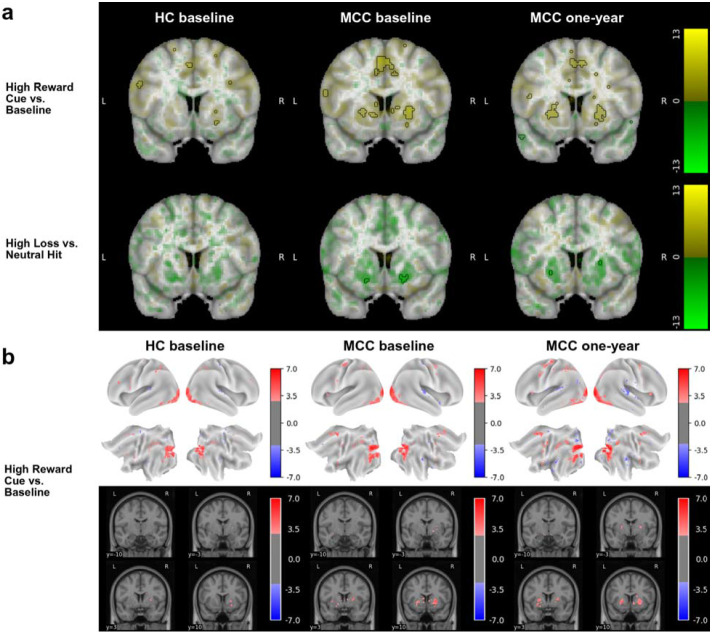

MID Task

During all cue contrasts, activation in the bilateral basal ganglia was observable in all three participant groups, though only reached statistical significance in the High Reward Cue vs. Baseline contrast (Figure 2, eFigures 5,6).32 During the reward vs. missed reward feedback contrast, activation in the bilateral basal ganglia is observed, while during all other feedback contrasts, deactivation in the bilateral basal ganglia and insula is observed, though only statistically significant in the high loss vs. neutral hit contrast in the volumetric analysis (Figure 2, eFigures 5,6). No difference in activation between the groups at baseline (HC n=23, MCC n=35) or between the two timepoints of the MCC group (n = 21 for High Reward vs. Neutral Hit and High Loss vs. Neutral Hit contrasts; n=22 for all other contrasts), and no effect of cannabis use frequency change on one-year activation of the MCC group were noted at the statistical significance threshold.

The findings of the study are corroborated by the results of the control group and by the brain activation patterns observed at both timepoints. Brain activation differences were not found between healthy controls and MCC participants at baseline, suggesting that the MCC group did not differ significantly at baseline from those who were not intending to use cannabis, thus addressing some of the limitations in previous studies. The working memory and inhibitory control tasks yielded statistically significant canonical activations in the control and MCC group at baseline and in the MCC group at the one-year timepoint.20,28,48,49 The reward processing task also yielded canonical activations for the cue contrasts.28,29,32,50,51 Activations to the feedback contrasts were also in line with what has been observed in the past, though the literature is less consistent in regards to the feedback contrast.29,50,51 Of note, only two of the MID contrasts reached statistical significance. This suggests that the response to the task was more heterogeneous in this participant sample, and perhaps a larger sample or a differently designed reward task would have been needed to achieve more robust activation. It was recently noted that the MID task has low reliability, with the most consistent contrasts being those involving an implicit baseline, which is consistent with our limited findings.52 Overall, the activation patterns of all three tasks were consistent with those observed in the literature, demonstrating that in the comparison across time, brain activation from the desired cognitive processes is being compared.